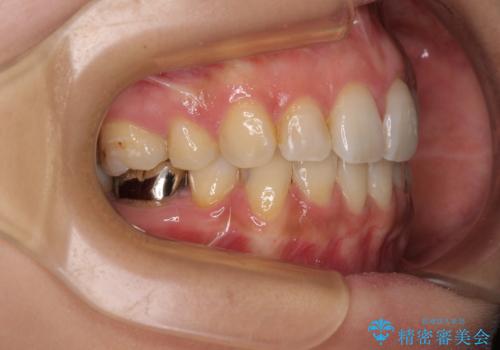

デコボコと口元の突出感 ハーフリンガルでの抜歯矯正

- 矯正装置

- ハーフリンガル

- 前歯のデコボコと上顎の前突感による口の閉じにくさを気にして来院された患者様です。

目立たない装置を希望されたので、上顎が裏側装置のハーフリンガルを選択し、上下左右の小臼歯(計4歯)を抜歯して矯正治療を行うこととしました。